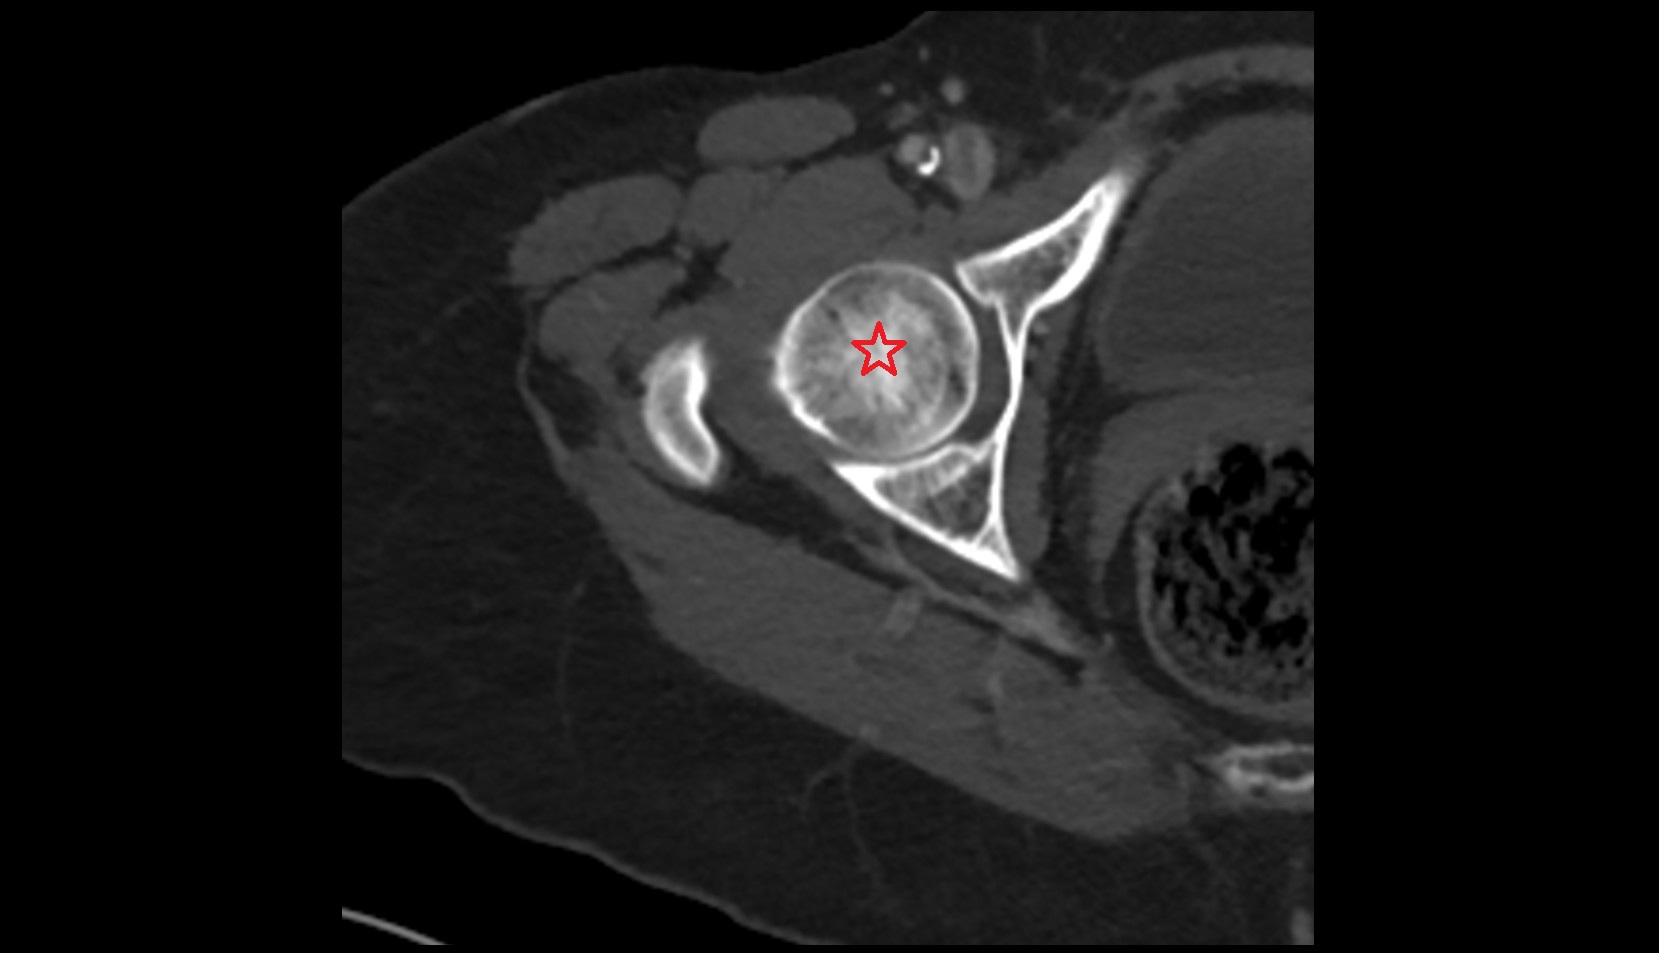

- Head of femur

- Acetabulum

- Hip joint